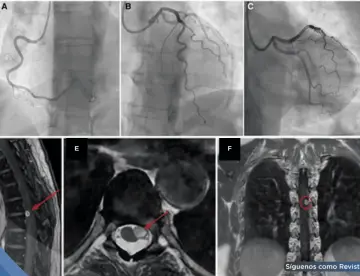

<content:encoded><![CDATA[<div><img src="https://blob.medicinaysaludpublica.com/images/2026/05/04/sacs-20--1089-300e16cb-focus-0-0-360-276.webp" alt="Hemorragia pulmonar por trombosis de vena cava simula sangrado digestivo en paciente en hemodiálisis " title="Hemorragia pulmonar por trombosis de vena cava simula sangrado digestivo en paciente en hemodiálisis "></div><p>Un hombre de 45 años con enfermedad renal crónica en hemodiálisis ingresó con aparente hematemesis e inestabilidad hemodinámica. Aunque el cuadro sugería un <strong><a href='https://medicinaysaludpublica.com/tags/sangrado/28213' target='_blank'>sangrado</a></strong> gastrointestinal superior, los estudios endoscópicos fueron inconclusos.&nbsp;</p>

<p>La tomografía torácica y la <strong><a href='https://medicinaysaludpublica.com/tags/broncoscopia/54407' target='_blank'>broncoscopia</a></strong> confirmaron una hemorragia pulmonar secundaria a trombosis de la vena cava superior, evidenciando un diagnóstico poco frecuente que puede imitar una emergencia digestiva.</p>

<h1><strong>Evaluación inicial: Sin evidencia de <strong>sangrado</strong> digestivo activo</font></strong></h1>

<p>La endoscopia digestiva alta mostró várices esofágicas pequeñas y gastropatía erosiva, pero sin <strong>sangrado</strong> activo que justificara la gravedad del cuadro. Este hallazgo obligó a ampliar el enfoque diagnóstico, considerando causas no gastrointestinales.</p>

<p>En este contexto, la tomografía computarizada de tórax reveló un hallazgo clave: trombosis de la vena cava superior con abundante circulación colateral mediastínica. Además, se evidenciaron áreas de consolidación alveolar compatibles con hemorragia pulmonar y un derrame pleural derecho.</p>

<strong>Confirmación diagnóstica</font></strong></h2>

<p>La <strong>broncoscopia</strong> fue determinante al identificar <strong>sangrado</strong> activo en el árbol bronquial derecho con presencia de coágulos adheridos, confirmando que la fuente del <strong>sangrado</strong> era respiratoria y no digestiva.</p>

<p>Este fenómeno explica cómo la sangre proveniente del tracto respiratorio puede ser deglutida o expulsada durante episodios de arcadas, simulando una hematemesis y generando confusión diagnóstica.</p>

<strong>Claves fisiopatológicas: Cuando la trombosis venosa desencadena hemorragia</font></strong></h2>

<p>La trombosis de la vena cava superior genera aumento de la presión venosa proximal, lo que favorece la formación de vasos colaterales frágiles en el mediastino y árbol bronquial. Estos vasos pueden romperse y provocar hemorragia pulmonar.</p>